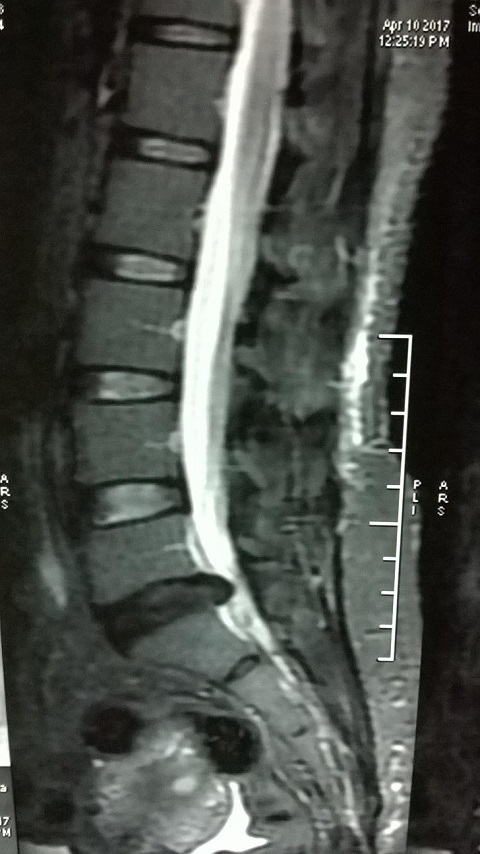

MRI of Geetanjali Behere